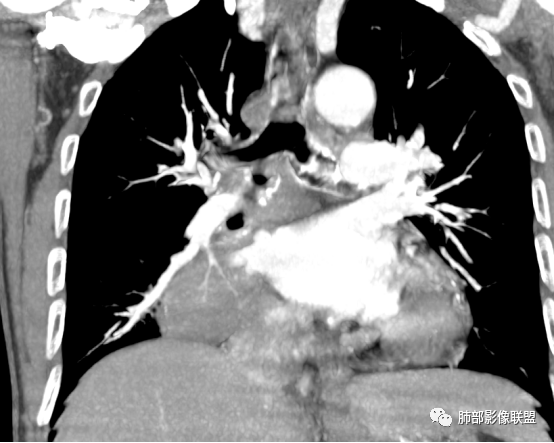

这是支气管,注意看视频支气管连续性的变化。如果上面的支气管完全堵塞,下面的支气管如何解释?

大家考虑这个是支气管腔内占位?引起远端阻塞?还是外围为主病灶侵犯支气管?

南边:个人倾向于外周为主病灶,腔内改变是继发的。原因:病灶围绕支气管,腔内远端无明显阻塞性不张。

边缘偏平直,内部血管走形自然,一般提示包绕为主。

支气管的堵塞也是让我觉得奇怪,当然这种最终支气管镜很直接。

(1)病灶形态和分布:双肺散在点片影,可见树芽征。右肺下叶内基底段实性密度团块状影,底部坐落膈面、浅分叶,略呈圆锥形沿血管支气管束探及肺门,可疑“支气管爬行征”。奇食窝区分出子灶。病灶轻中度强化不均,斑片状低密度无强化区,疑坏死,未见钙化。右肺门及淋巴结肿大。

(2)支气管和血管:右肺支气管分支管壁弥漫性增厚,中间段支气管散在结节样凸起,右肺下叶内基底段支气管闭塞,但远端可疑复出。余病灶围绕支气管腔内远端无明显阻塞性不张。内部血管走形自然,提示包绕为主。